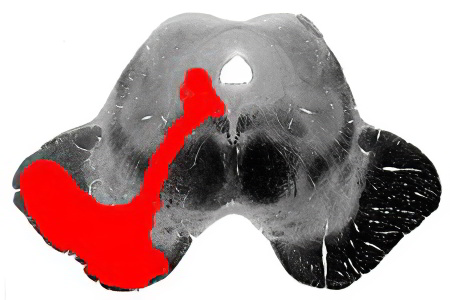

Периферические парезы VII пары краниальных нервов

Периферические парезы возникают при повреждении нервных волокон лицевого нерва в периферической части, что приводит к частичной утрате двигательной функции. Существует несколько типов повреждений вдоль пучков лицевого нерва (после его ядра, в канале пирамиды височной кости, в тканях челюстно-лицевой области).

Периферические поражения лицевого нерва проявляются следующими симптомами:

Топические симптомы описывают вовлечение в патогенез конкретных участков лицевого нерва, расположенных на различных участках его пути (от головного мозга до конечных нейронов — аксонов или дендритов).

Альтернирующий синдром Мийяра-Гюблера

Этот синдром указывает на поражение ядра лицевого нерва на уровне ствола и волокон пирамидного пути, проявляясь:

- на стороне поражения — парезом лицевого нерва;

- на противоположной стороне — гемипарезом (ослаблением движений) или гемиплегией (параличом половины тела).